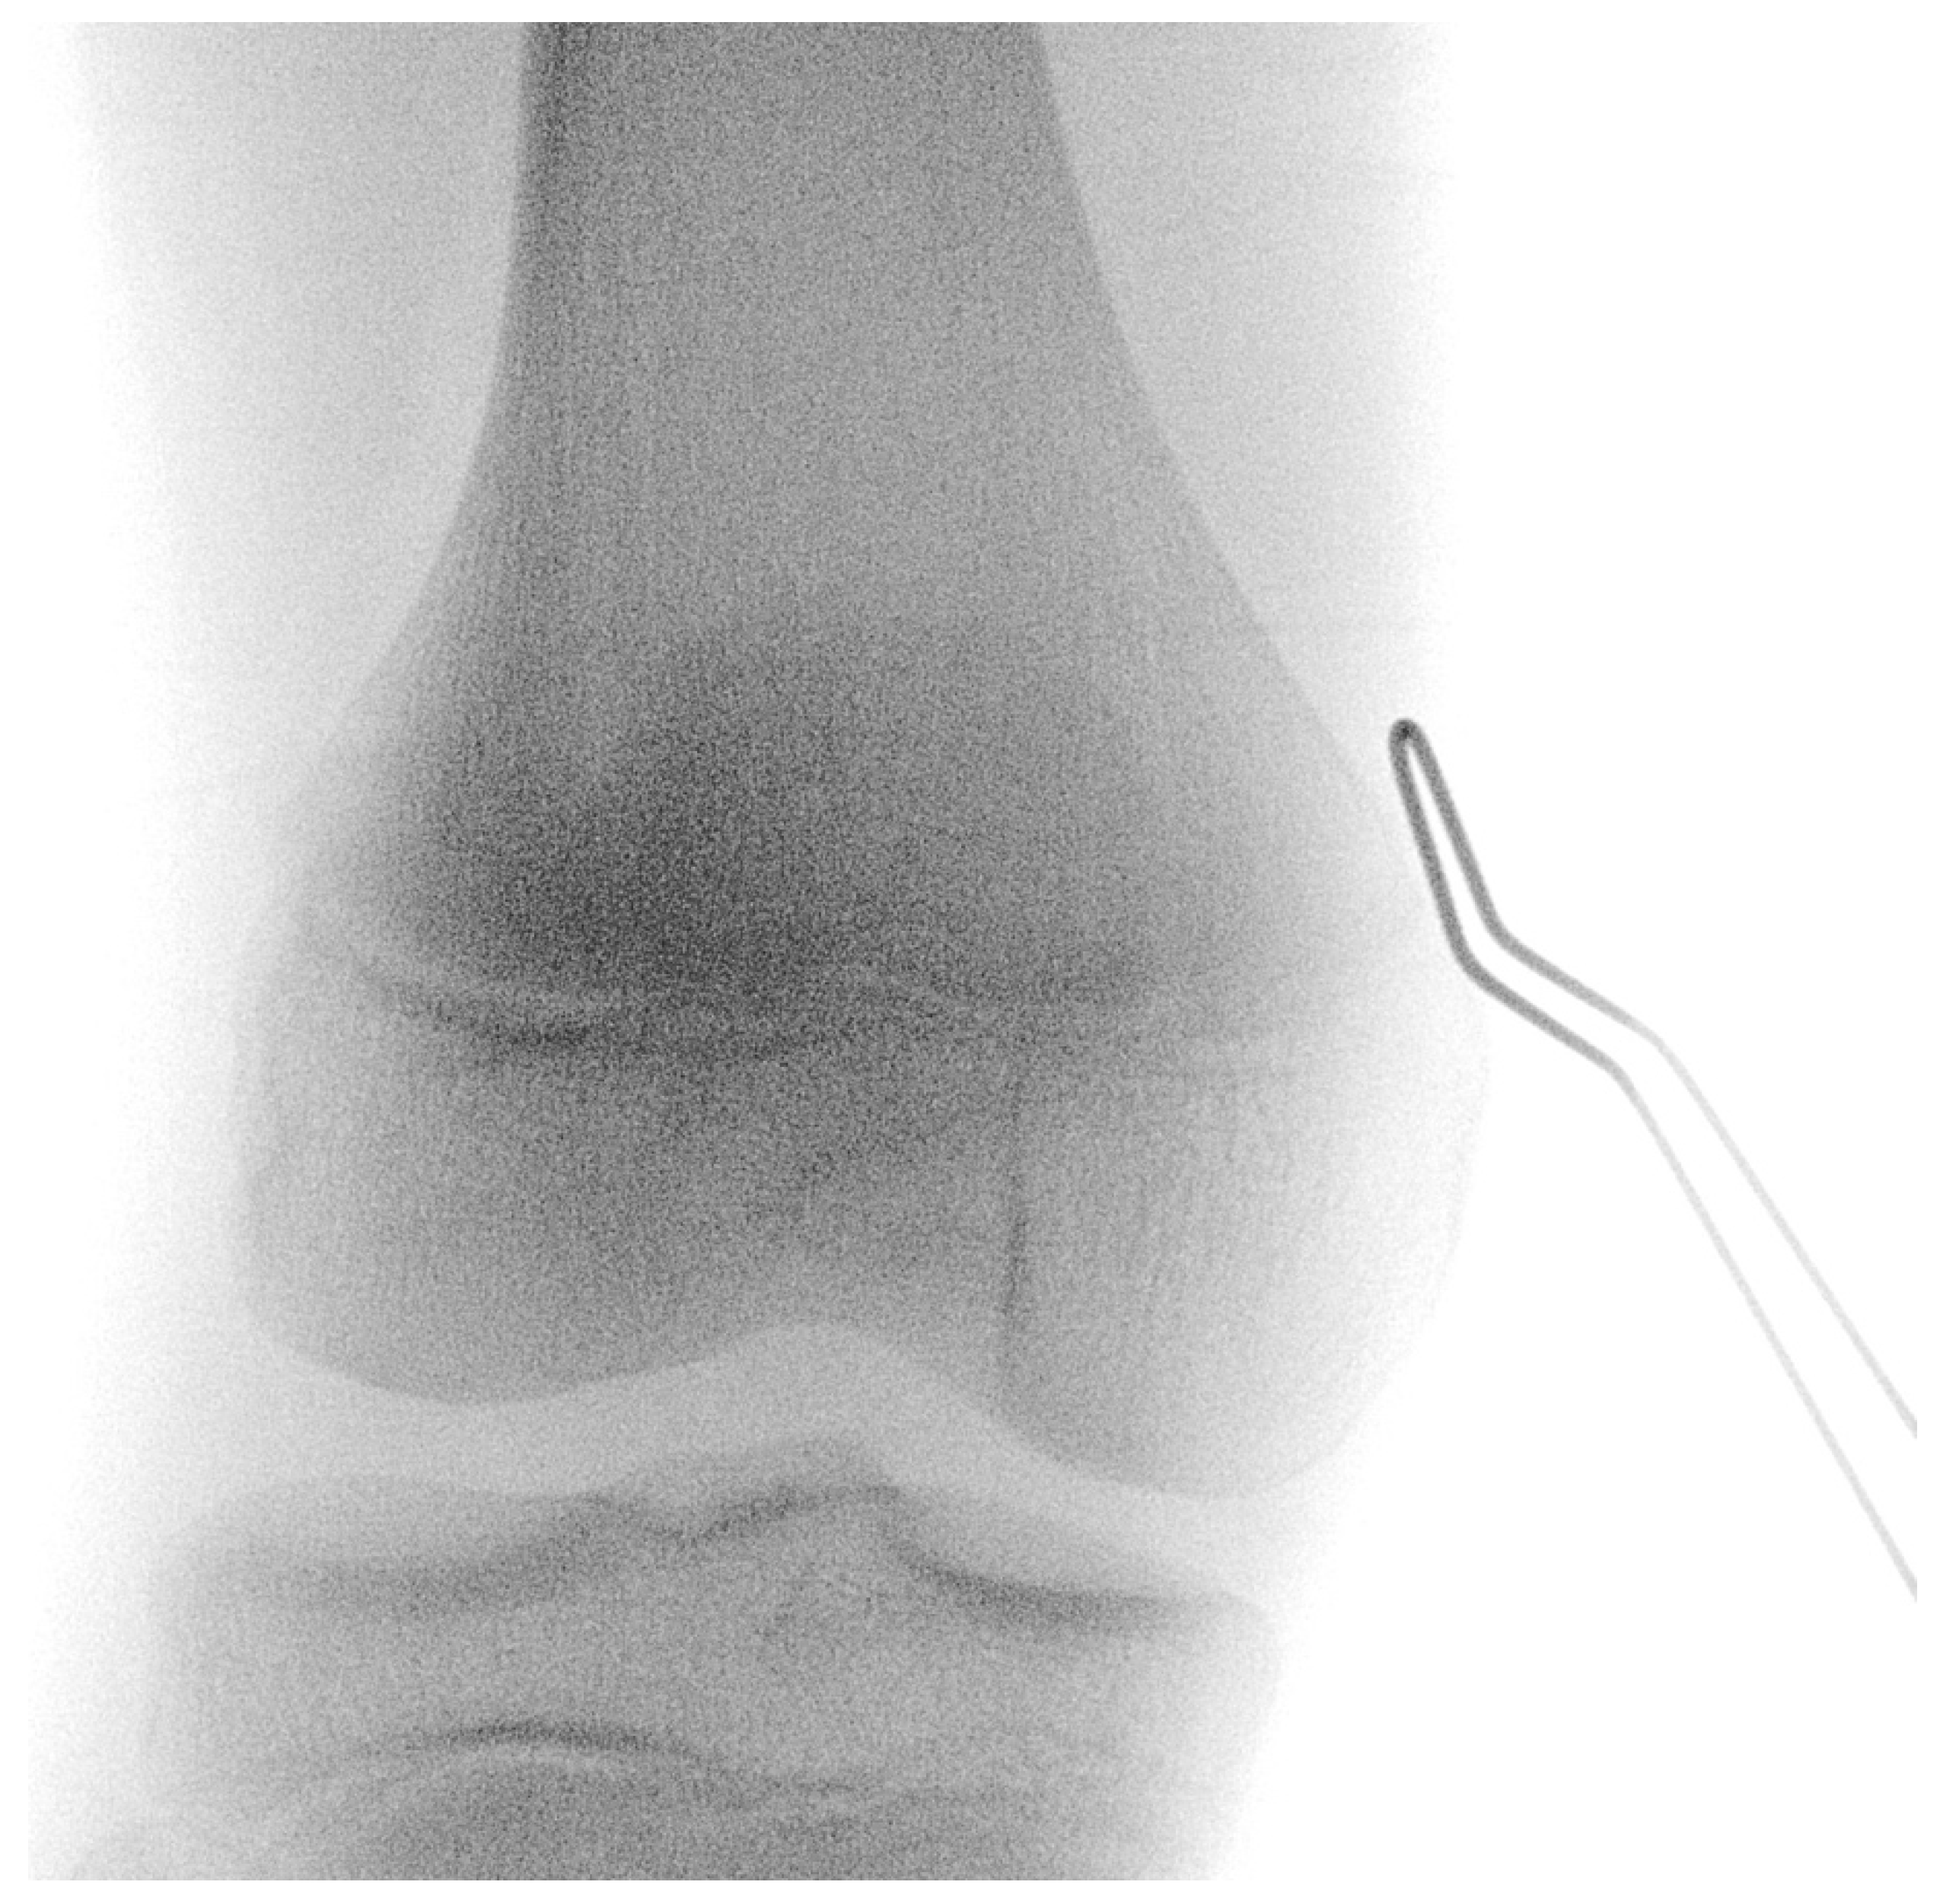

2.2. Surgical Technique